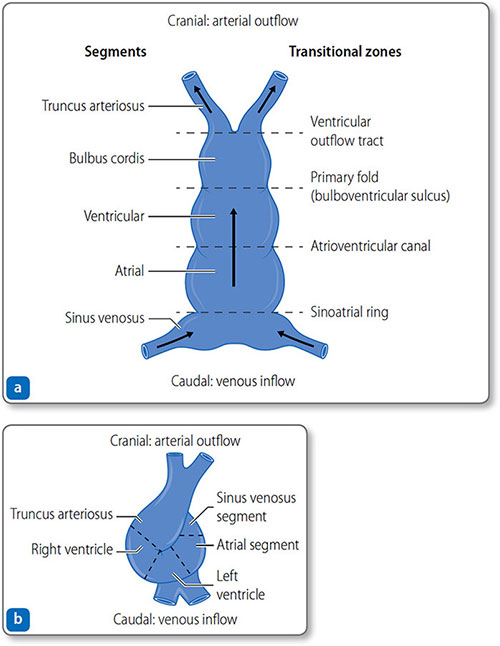

- Day 21: the two tubes fuse to form a single-chambered heart with five segments that develop into chambers (Figure 1.17 and Table 1.5). Myocyte rhythmic activity begins before tube fusion

On days 23–28, the growing tube folds and loops to the right (Figure 1.17b) to produce:

Figure 1.17: The heart tube. (a) Day 21: the heart tube has five distinct segments and four transitional zones. (b) Day 23–28: the tube folds and loops to resemble the mature heart.

|

- Cranial segments: primitive ventricle and truncus arteriosus (the outflow tracts).

Once aligned, the atrial and ventricular segments begin to expand, differentiate and trabeculate. Externally, the heart starts to resemble the mature structure but internally remains a relatively simple folded, looped tube until the chambers and outflow tracts are divided by septation, the formation of tissue septa.